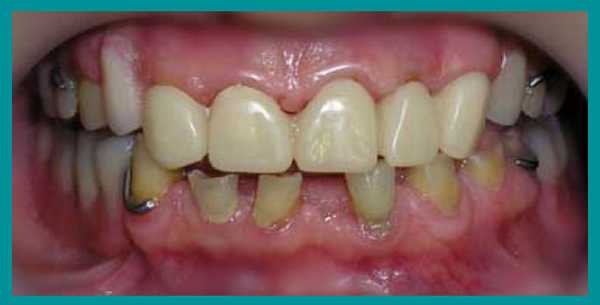

После фиксации металлокерамических коронок на постоянный цемент, коррекции и установки бюгельных протезов на кламмерах, пациент получил рекомендации по уходу за зубными протезами и проведению личной гигиены полости рта. План лечения был выполнен. Рекомендовано профилактическое посещение стоматолога каждые четыре месяца.

Итог лечения

От начала лечения и до его завершения прошло больше года. В итоге пациент получил эстетичные и очень функциональные зубы, исчез психологический дискомфорт. Одновременно была решена проблема неправильного прикуса, восстановлена работа височно-челюстного сустава.